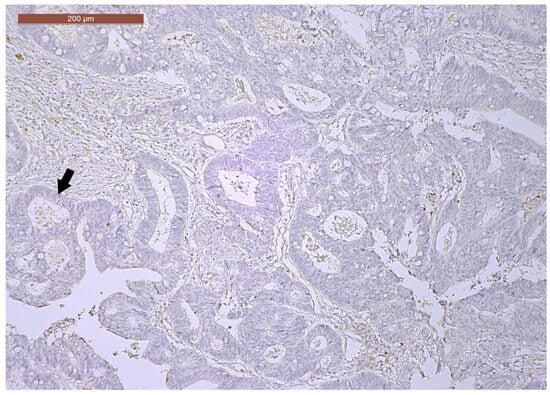

LVI was detected in 31 cases (51.7%), and perineural invasion (PnI) was identified in 20 cases (33.3%) (Figure 1 and Figure 2). EMVI and IMVI were registered in 31 (51.7%) and 21 cases (35%), respectively. Regarding Bd and PDC categories, a significant proportion of tumors were recorded as Bd1, while Bd2 was less common (49 cases; 81.6% vs. 7 cases; 11.7%) (Figure 3); moreover, a large proportion were classed as the PDC1 grade (Figure 4), while the PDC2 grade was less common (55 cases; 91.7% vs. 4 cases; 6.7%). The main clinicopathological characteristics of the study group are summarized in Table 4.

Figure 4. A few groups of tumor cells (arrows), consisting of at least five cells, located at the invasive tumor front in a ypT3-stage LARC case (PDC1) (H&E staining, 200×).